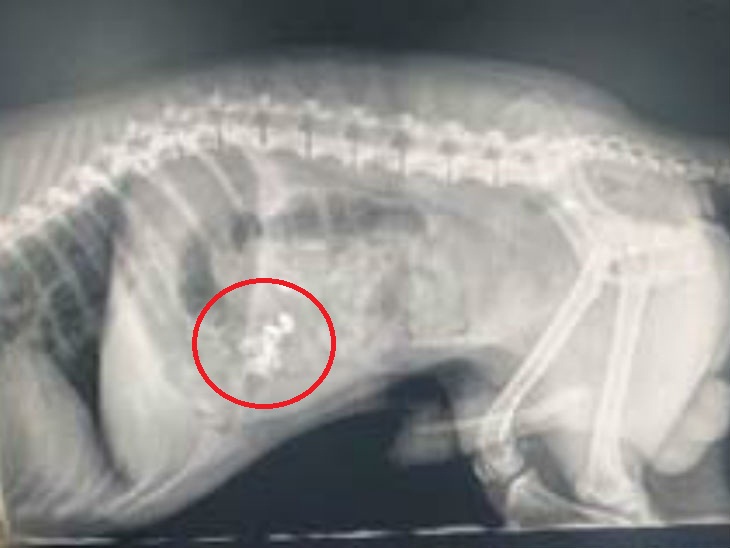

From www.divyabhaskar.co.in

Pet dog swallowed diamond earrings, Xray revealed the truth કૂતરો Dog Swallowed Earring Back This article will teach you what to do if your dog swallowed an earring so you can be sure they’re safe,. that’s one way your earrings might end up in your dog’s mouth, which leads you to worry that your dog ate an earring! dog ate an earring? Contact your veterinarian for guidance based on the size of. Dog Swallowed Earring Back.